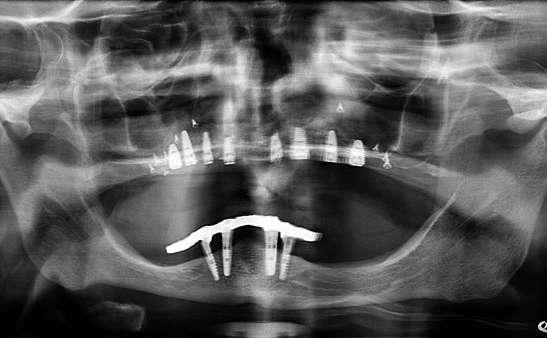

Figuras 3-6. Imágenes de un caso de prótesis atornillada en molar unitario inferior. Vemos el estado de los tejidos blandos gingivales tras la segunda fase y colocación del transepitelial unitario y la radiografía. En las imágenes inferiores (5 y 6) observamos el caso a los 4 años y 10 años de seguimiento, con estabilidad completa de los tejidos óseos peri-implantarios.

Figuras 7-10. En las dos imágenes superiores (7 y 8) observamos la realización de la prótesis cementada mediante un bioplilar fresado a la altura gingival con la radiografía antes del cementado de la corona. En las imágenes inferiores (9 y 10) vemos la prótesis a los 7 años de seguimiento y a los 9 años transformada en una prótesis atornillada al perderse la pieza anterior al implante y realizarse un puente con el nuevo implante. En este caso, el nivel óseo permanece estable con el paso del tiempo.